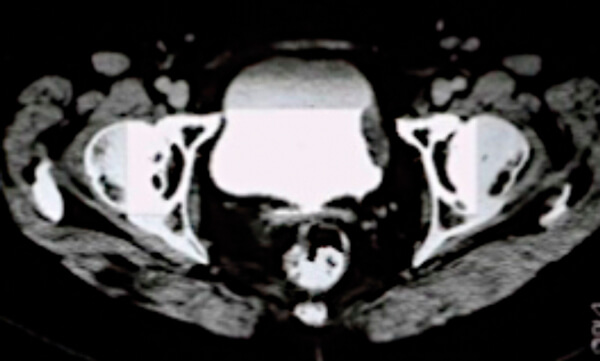

- What does the scan in Figure 1 show?

1. This is a CT urogram of the pelvis demonstrating a filling defect in the bladder suspicious for muscle invasive bladder cancer. A CT chest is needed to complete the staging.